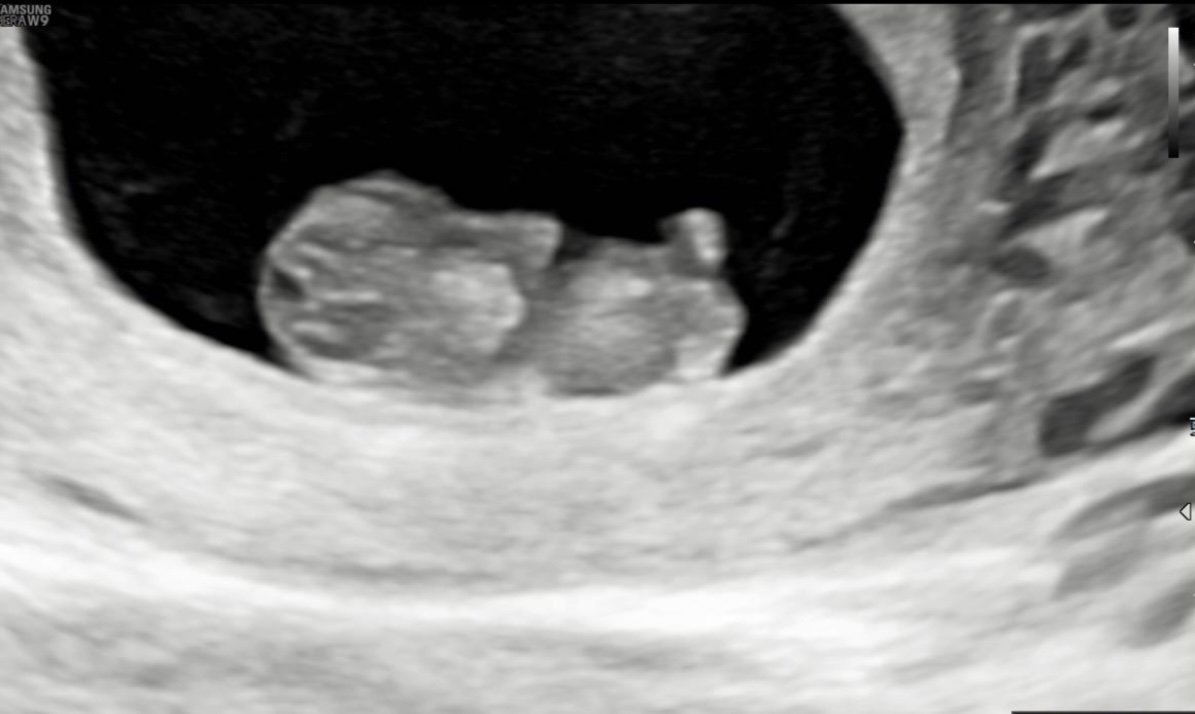

Bany ооо не мога да повярвам колко добре се вижда! Heart нямам търпение и аз да видя същото! А защо се пие дуфастон?

И аз днес бях . Около 10 седмица съм. Моето се е хванало за главата 😃😃😃😃